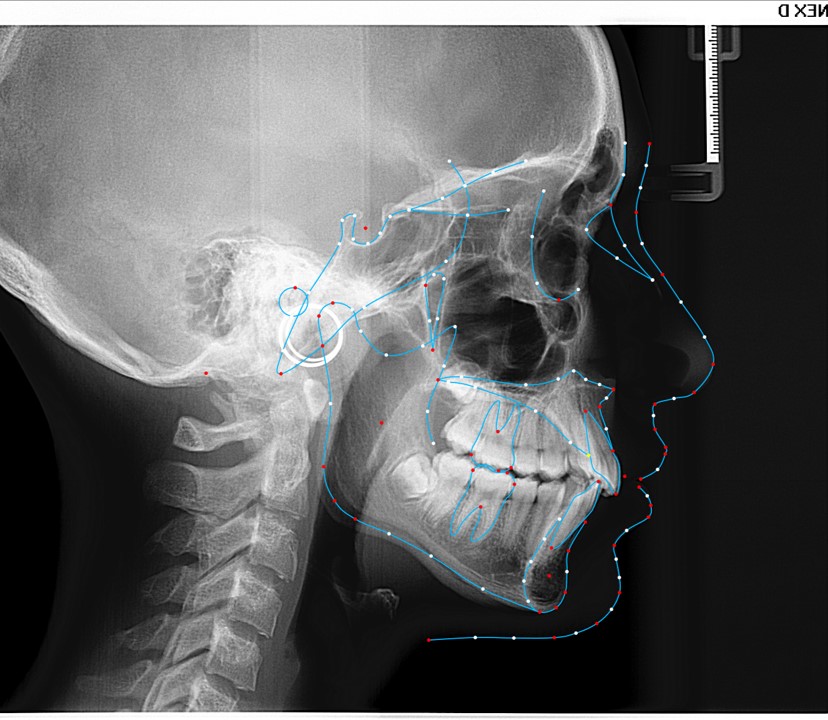

Chief complaint: We present the case of a 12-year-old female patient who came for an orthodontic evaluation, motivated by a family history of treatment. Clinical and radiographic analysis revealed a skeletal Class II malocclusion with molar and canine relationships also in Class II, moderate crowding in both arches, a deviation of the dental midline, and ectopic eruption of tooth 13. No functional issues with breathing or swallowing were observed, and oral health was generally good. A slight mandibular retrusion was noted in the soft tissue profile. A treatment plan was proposed using the Angel Aligner Pro system, aiming to correct dental misalignments and improve facial harmony through a minimally invasive, growth-adapted approach.

Clinical examination and diagnosis

- Woman ; 12/3 years

- Skeletal Class II

- Molar and canine Class II

- Upper and lower dentoalveolar compression

- Increased overjet and overbite

- Upper midline deviated 0,5 mm to the right

- Moderate upper and lower crowding